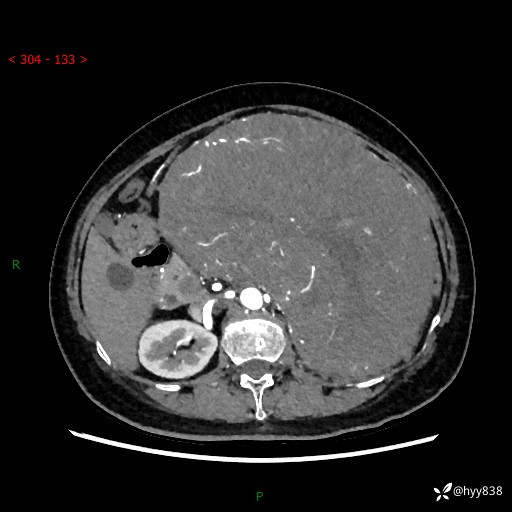

据说只有腹膜后,才能见到如此巨大的肿块---(有结果)

主诉:发现腹膜后占位1周

简要病史:患者1周前因头晕在当地第二人民医院检查发现左侧腹膜后区巨大富血供占位性病变,患者自诉腹部稍硬,无其他不适,无血尿,无腰痛等不适,患者为求进一步治疗来我院,门诊以“腹膜后占位性病变”收入我科。 起病以来,患者精神、饮食、睡眠可,大便正常,小便如上述,体力体重无明显改变。

临床诊断:腹膜后占位

腹部CT增强(动脉期+静脉期 ) ---平扫外院